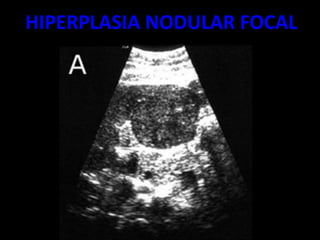

HIPERPLASIA NODULAR FOCAL